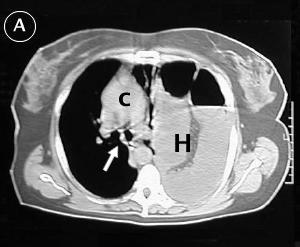

Corte Tomográfico A

Flecha: carina, observe el desplazamiento del mediastino hacia la derecha.

c: corazón desplazado a la derecha.

H: El hemitorax izquierdo ocupado por las asas intestinales, ausencia de parenquima pulmonar